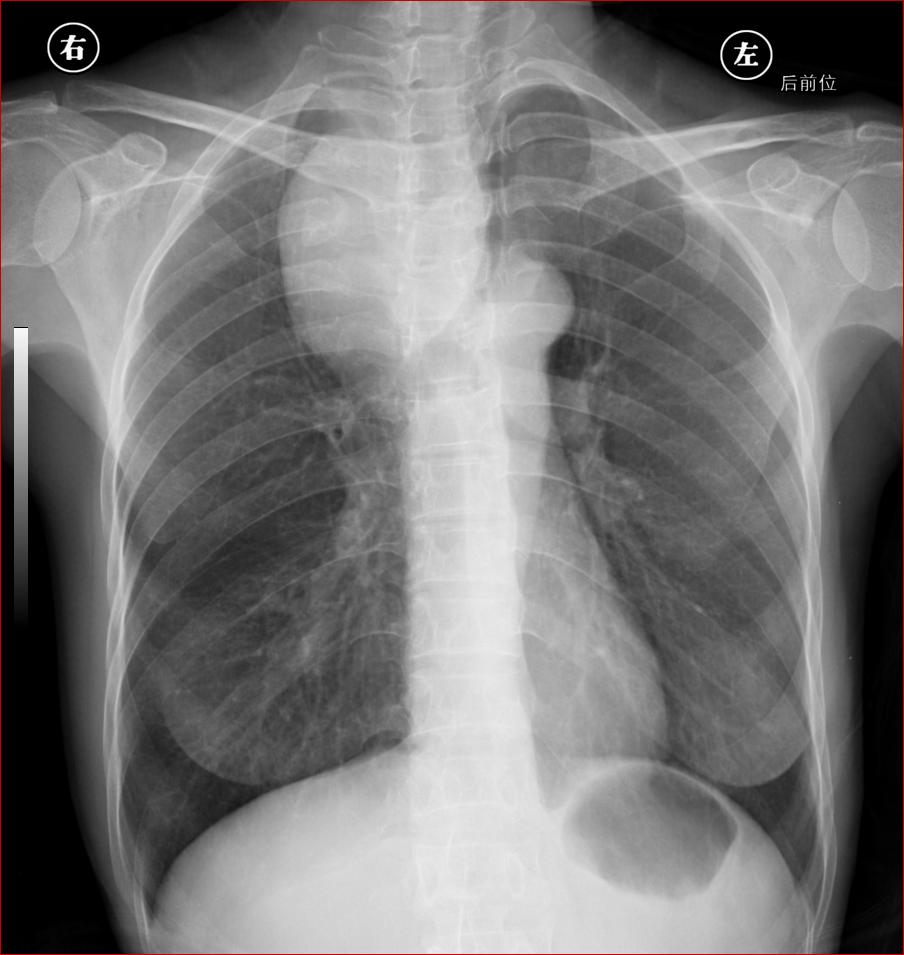

标题: CT17110:F56Y,纵隔囊肿;胸腺?淋巴?请各位老师看看 [打印本页]

女性患者 56 咽痛伴声嘶10+天入院。

右上纵隔囊性占位性病变;考虑支气管囊肿可能。

右上纵隔囊性占位性病变,建议强化。

右上纵隔囊性占位性病变;考虑支气管囊肿可能。建议ct增强扫描